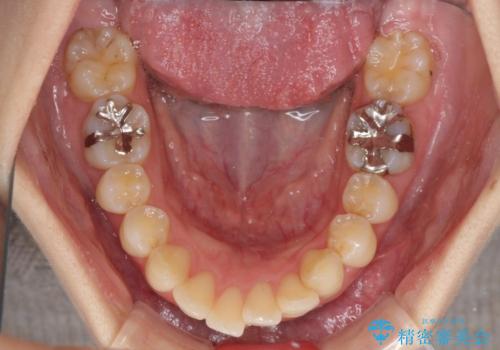

上下左右第一小臼歯4本を抜歯し、ワイヤー装置にて口元を引っ込めるよう矯正治療を行うこととしました。

ご友人などがびっくりするほど口元の突出感を改善することができ、患者様には大変満足していただきました。